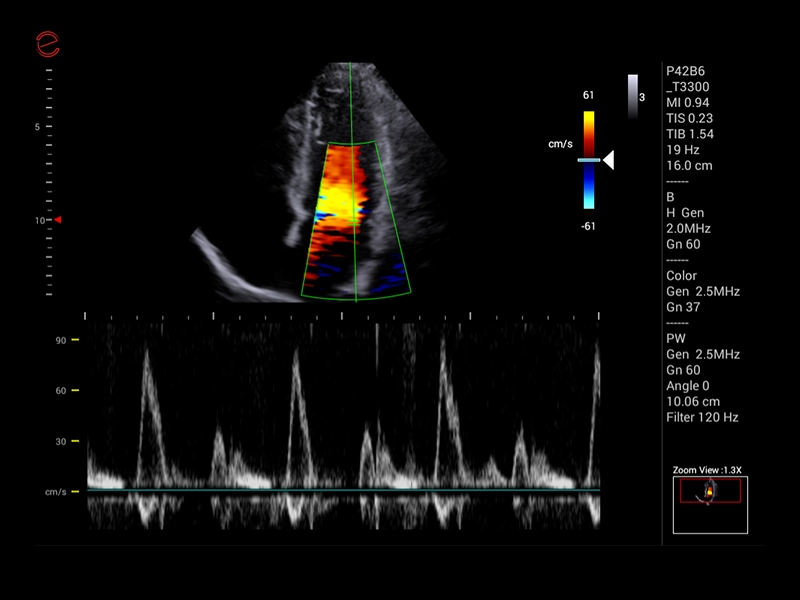

MyLab™C30 - Doppler - CW

MyLab™C30 - Doppler - CW